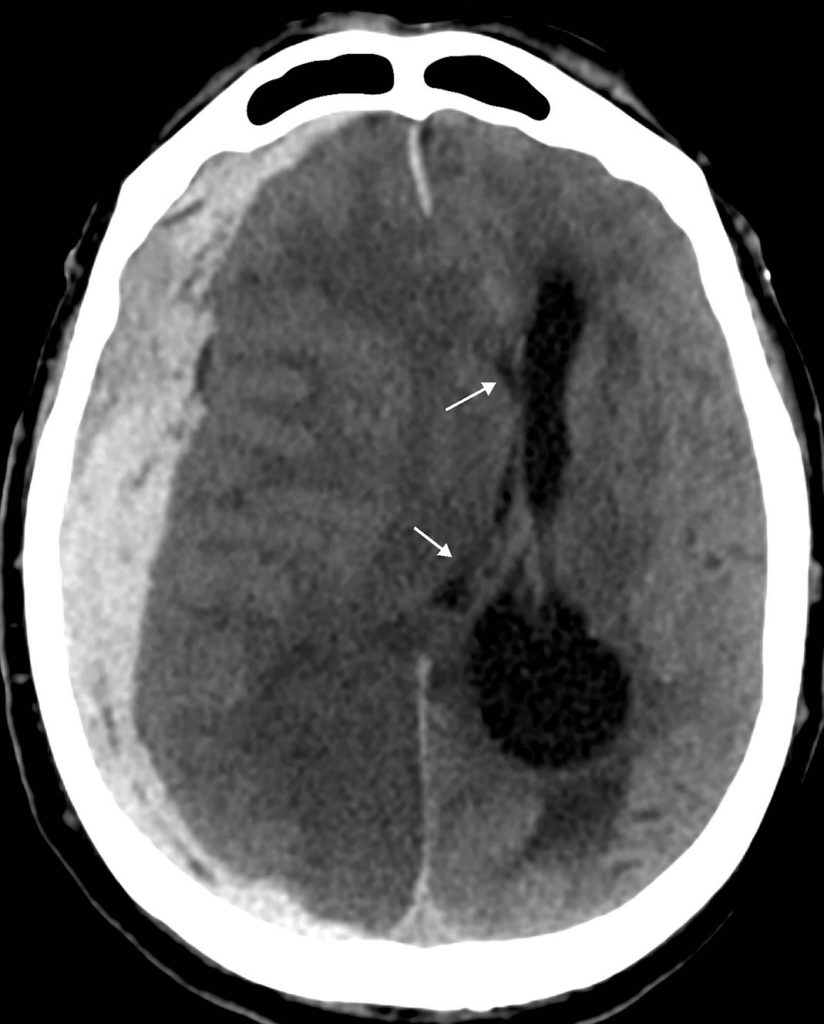

C’est une collection hyperdense en scanner en forme de croissant, souvent étendue, sous la table osseuse (figure 58.2), mais parfois le long de la faux du cerveau ou de la tente du cervelet, limité par les sinus duraux intracrâniens.

Fig. 58.2. Scanner cérébral. Hématome sous-dural aigu avec signes d’engagement sous-falcoriel.

Scanner sans injection en coupe axiale : volumineuse collection hyperdense de la convexité droite refoulant le parenchyme cérébral et responsable d’un important effet de masse avec déplacement des ventricules latéraux et des structures médianes (flèches).

Source : CERF, CNEBMN, 2022.

L’effet de masse est variable, pouvant aller jusqu’à des signes d’engagement temporal ou sous-falcoriel (cf. chapitre 55).